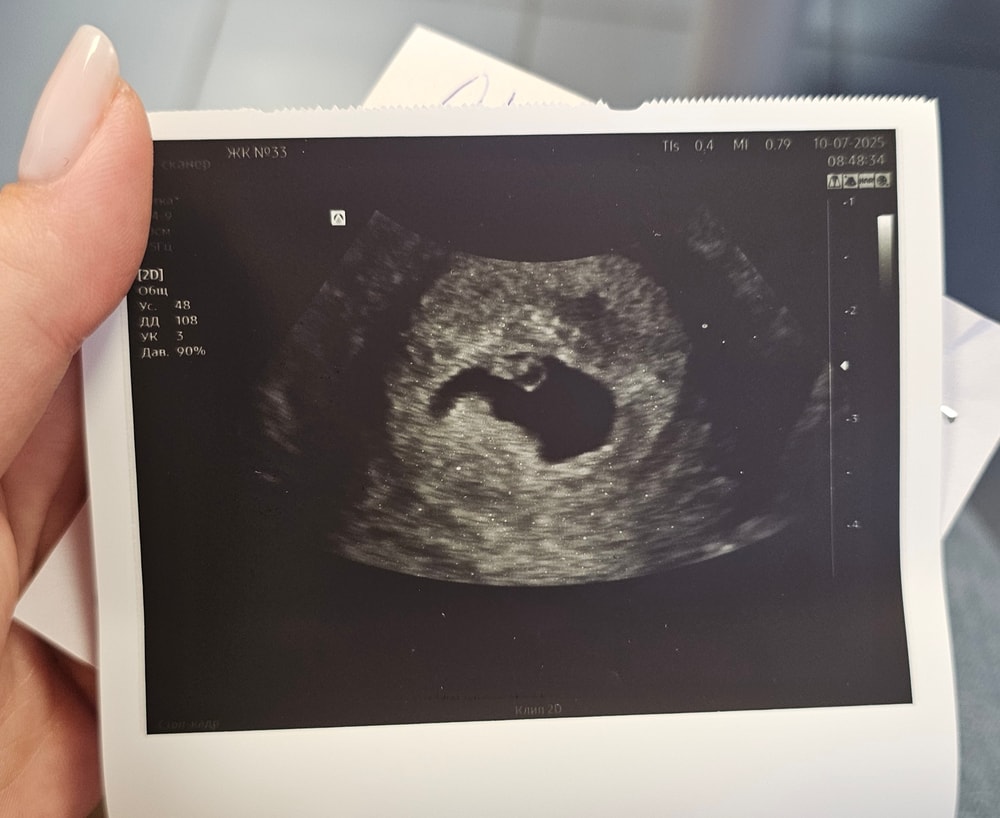

Сегодня сделали экспресс узи в жк. Сначала абдоминально. Узистка меня напугала...Спросила срок, говорит раздевайтесь, маленькое, похоже на замершую. И через минуту, уже при вагинальном узи: все хорошо, сердце бьётся. Плодное 17,2. Срок 4+3. По мес ровно 7 недель.

2.07 ПЯ 4мм

10.07 ПЯ 17,2 мм СБ+